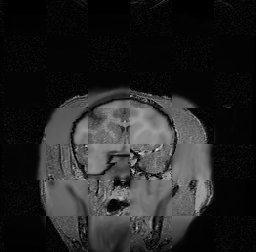

For each of the 10 subjects, we show checkerboard slices in each direction (1) before registration, first row; (2) after rigid->scaleversor->affine registration, second row; and (3) after BSpline registration, third row.

Issac

Issac is a good example of BSpline registration failure.

Ron noted, the reason might be that Issac had his mouth open, unlike most of the subjects registered successfully.